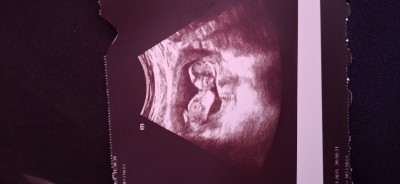

Kızlar sizce cinsiyeti ne bilen yazarsa çok mutlu olurum

Gebelik haftası 13+2